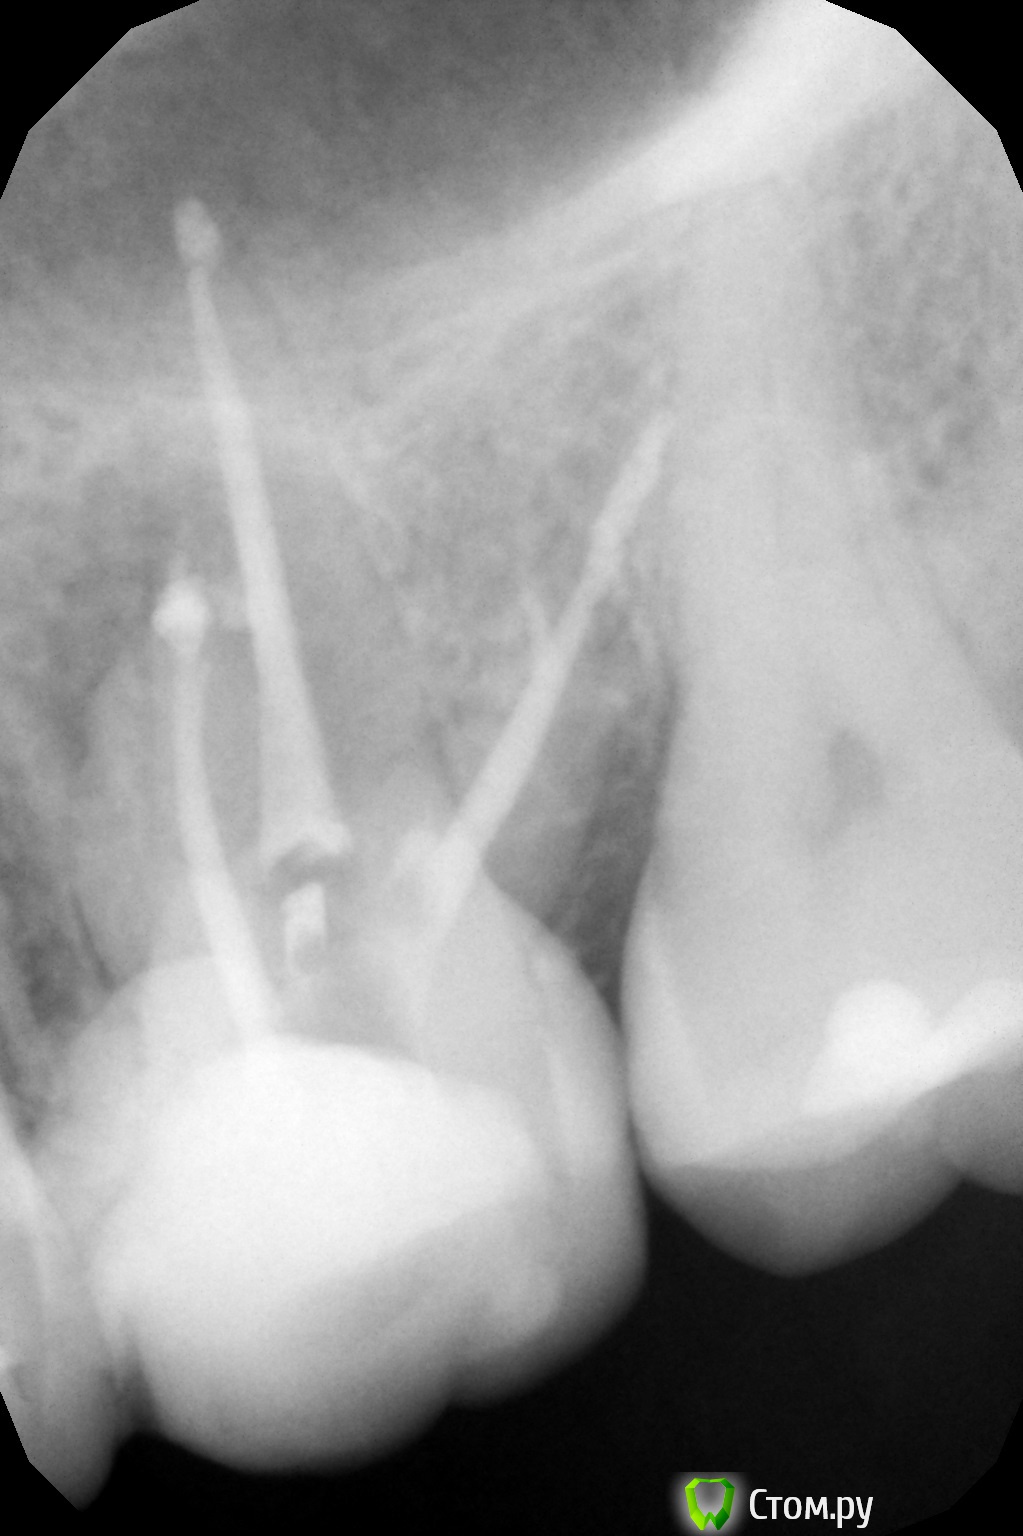

oksanab Опубликовано 9 октября, 2014 Поделиться Опубликовано 9 октября, 2014 (изменено) мне лечили 26-й зуб и медсестра озвучила, что нет 40-го и 38-го штифта .В итоге врач поставил просто эндометазон без гуттаперчей. Это я узнала, когда мне зуб вскрыли и стали перепломбировывать один канал, ввиду того, что паста там была не застывшая, мягкая. Является ли это ошибкой терапевта, когда паста мягкая в канале? . Плохо ли, когда эндометазон без гуттаперчи(судя по всему не было 40-го )? И почему ,как вы думаете, уже другой терапевт перелечила только центральный канал и не тронула остальные, хотя я просила об этом(потому что ортопед попросил). Она только загерметизировала остальные два канала(возможно апексом, не знаю, а вот центральный канал апексом верхушку корня залила). Достаточно ли этого, или лучше все-таки перепломбировать и два остальных канала?(в одном из них судя по всему перфорация, на другом - лекарство выведено за канал ,а может эндометазон за канал с лечебной целью выведен.... В выписке предыдущий врач не отметил, какое конкретно лекарство за каналом было выведено. Прилагаю снимки, на первом три канала 12 лет назад, на втором и третьем - перелечивание и пломбировка эндометазоном всех трех каналов(просто два снимка в разных клиниках ,но суть одна), да еще и скол зуба появился небольшой(ортопеды говорят, поправимо), и на третьем снимке перепломбировали только центральный канал. Нормально ли перепломбировали хоть средний канал? на мой взгляд как-то верхушка его странно расширилась, была поуже на 2-м и 3-м снимке(пломбировали методом латеральной конденсации). Подскажите пожалуйста, что думаете? Изменено 9 октября, 2014 пользователем oksanab Ссылка на комментарий

Cleric Опубликовано 9 октября, 2014 Поделиться Опубликовано 9 октября, 2014 (изменено) В вашем зубе "пропущен" ещё один канал в переднем щечном корне. Зуб на адекватное перелечивание. В этом зубе минимум 4 канала. Изменено 9 октября, 2014 пользователем Cleric Ссылка на комментарий

Паращук Роман Опубликовано 10 октября, 2014 Поделиться Опубликовано 10 октября, 2014 (изменено) Сравните снимки.Ты видишь суслика? Нет? И я нет,а он есть! (с)ПиСи Пропущенный канал,перфорация,мат-ял за верхушкой. Зуб уже визу в плевательницу открыл.http://s020.radikal.ru/i708/1410/b7/ad9c402a2f4c.jpghttp://s43.radikal.ru/i099/1410/5f/23581663b182.jpg Изменено 10 октября, 2014 пользователем Паращук Роман Ссылка на комментарий